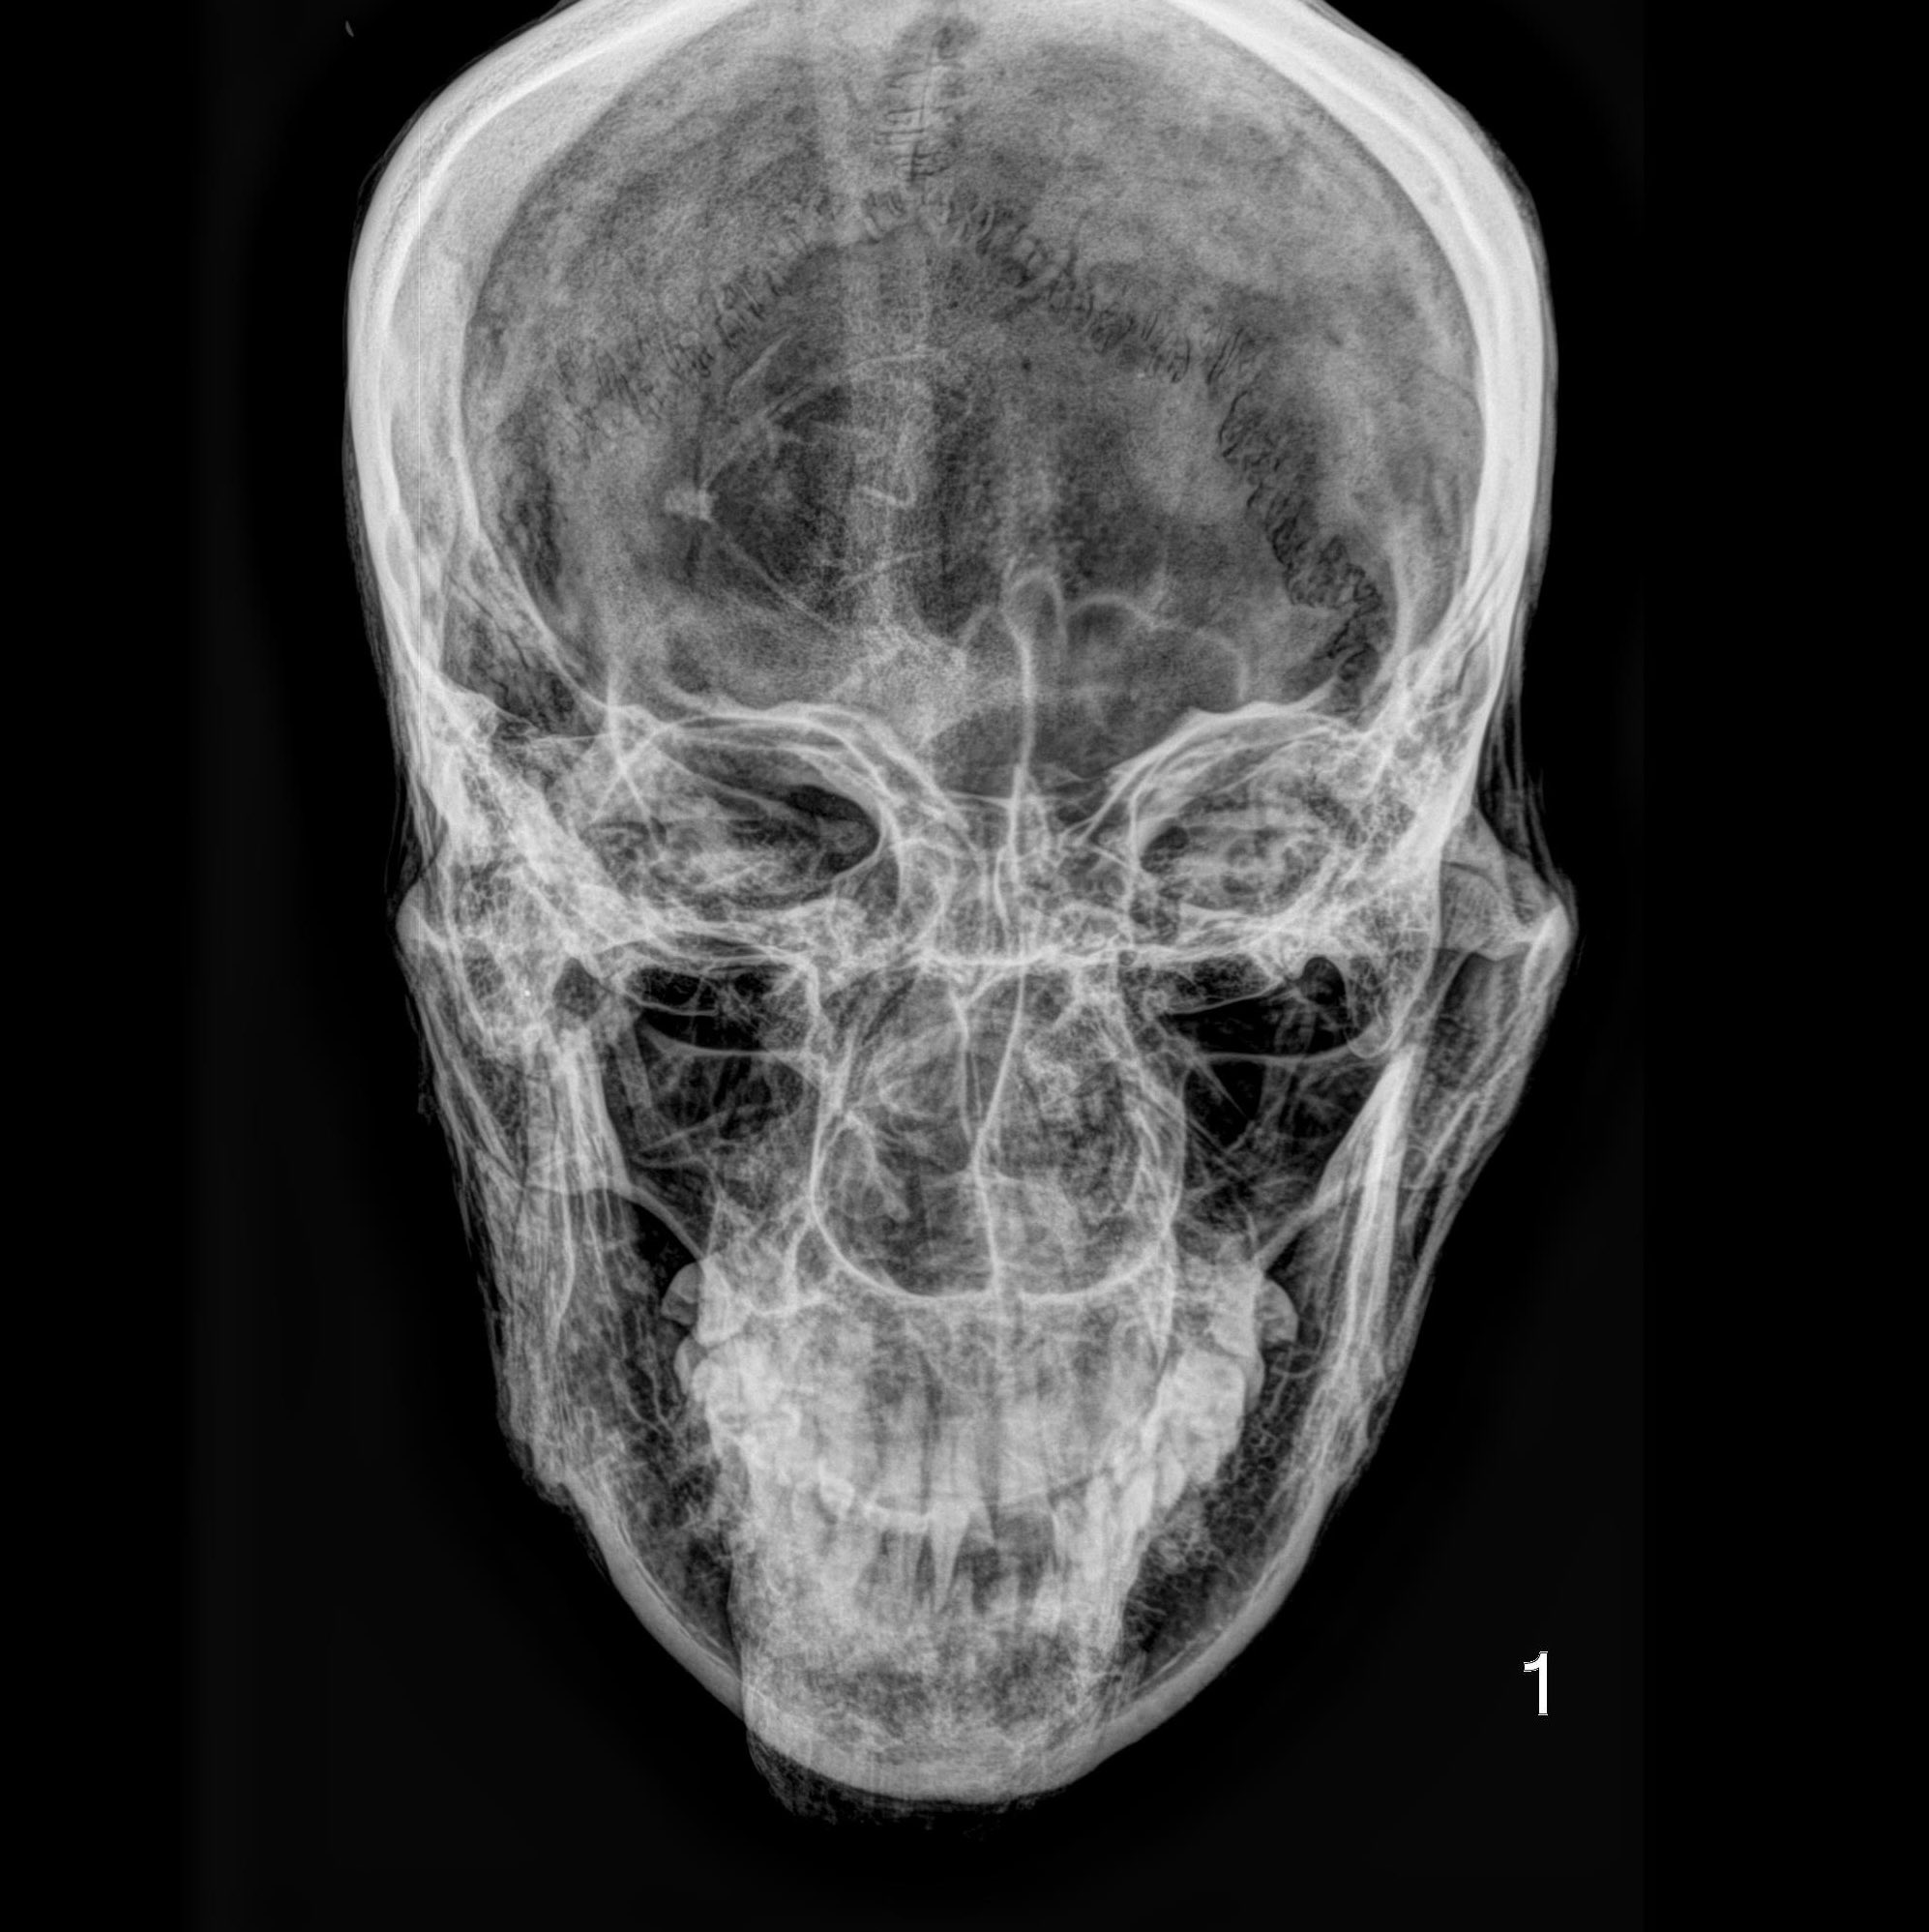

The methodology behind C14 analysis is as fascinating as the results it produces. Photographic images, X-ray images for analyzing internal structures and the graphical evaluation of C14 dating results offer in-depth insights into the condition and history of the examined individual. With cutting-edge techniques such as the Single Stage Accelerator Mass Spectrometer (SSAMS) and the Automated Graphitization Equipment AGE-3, even the smallest details can be deciphered.